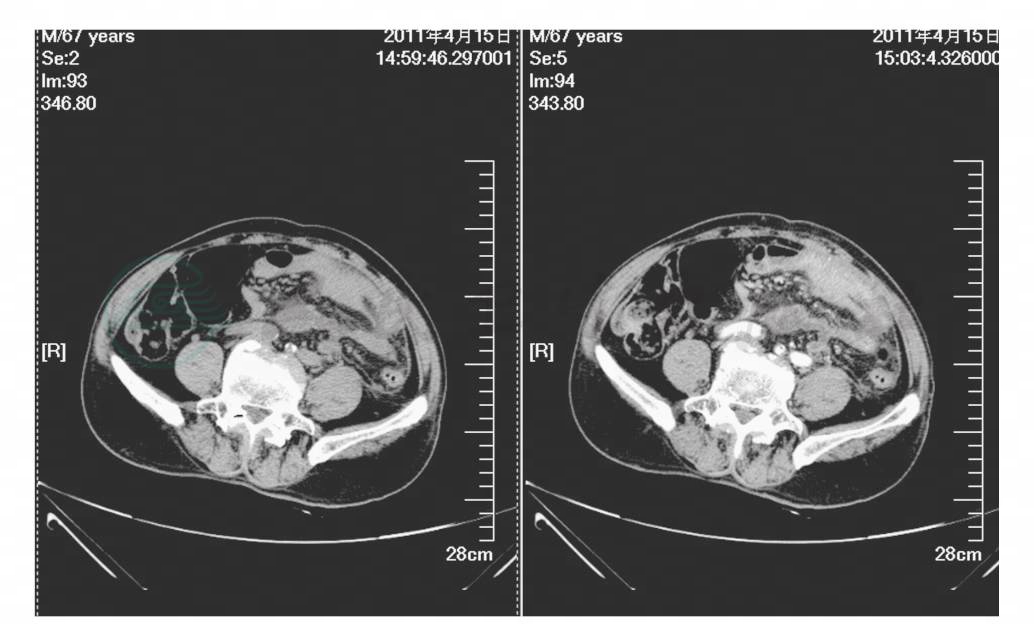

外院腹部CT示:左腰大肌低密度灶,性质待定。腹部CT增强示:左中下腹部分小肠炎性粘连,小肠高位不全梗阻,肠系膜局限脓肿可能性大,累及左侧腰大肌(图1,图2)。胸部正侧位片提示:双下肺纹理稍增强(图3)。

图1 腹部CT增强示左中下腹部分小肠炎性粘连,小肠高位不全梗阻(一)

图2 腹部CT增强示左中下腹部分小肠炎性粘连,小肠高位不全梗阻(二)